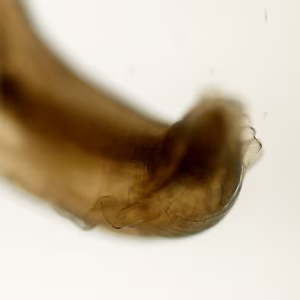

A state public health laboratory received three worms from a regional commercial laboratory for identification. The public health laboratory submitted the worms to the CDC/DPDx Team for diagnostic assistance. The submission form indicated that how and where the worms were collected was not provided by the commercial laboratory. Figure A shows all three worms for gross presentation and size determination. A dissecting microscope was used to observe morphologic features. Figures A and B shows two separate focal planes of the anterior of one worm; Figures C, D and E show three aspects of the tail. What is your diagnosis? Based on what morphologic features.

Figure C